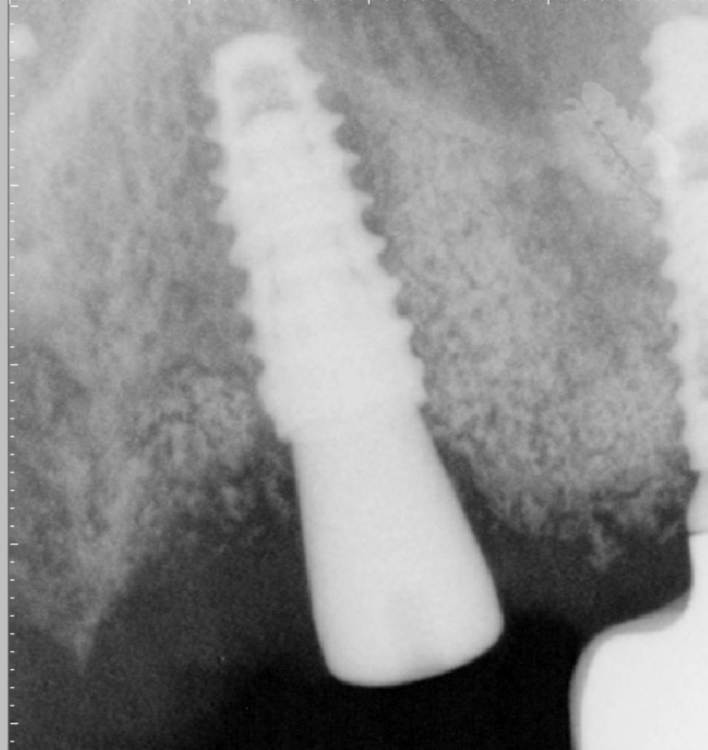

АнтонТЛТ Опубликовано 4 июня, 2021 Поделиться Опубликовано 4 июня, 2021 Жил да был имплантат 3.5мм, прижимался хорошо вместе с поджсаженной костью. Но в один момент ортопед со злобным техником решили его запротезтровать неоригинальным тибейсом в составе цирконевого моста. Имплантату это не понравилось и он решил, что ему пора на покой. И сделал себе харакири. А чтобы не сильно травмировать пациента, было решено удалить винт и имплантат. Затем сразу же поставить имплантат чуть короче и немного потолще. Время работы 50минут с учётом фотографий. 3 Ссылка на комментарий

Карен Аванесов Опубликовано 4 июня, 2021 Поделиться Опубликовано 4 июня, 2021 1 час назад, АнтонТЛТ сказал: Жил да был имплантат 3.5мм, прижимался хорошо вместе с поджсаженной костью. Но в один момент ортопед со злобным техником решили его запротезтровать неоригинальным тибейсом в составе цирконевого моста. Имплантату это не понравилось и он решил, что ему пора на покой. И сделал себе харакири. А чтобы не сильно травмировать пациента, было решено удалить винт и имплантат. Затем сразу же поставить имплантат чуть короче и немного потолще. Время работы 50минут с учётом фотографий. Антон, думаю дело не только в левой протетике, та как бэ кость которая была около имплантата, она как бы и не кость. Ортопеды, говорят пациентам на чем те экономят, когда голосуют за левые супраструктуры? Ссылка на комментарий